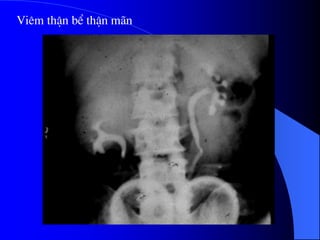

Viªm thËn bÓ thËn m·n

* NÂTM: tháûn nhoí khäng cán

xæïng bãn âäúi diãûn, båì läöi loîm,

nhu mä moíng khäng âãöu ngang

våïi mæïc âaìi tháûn, âaìi tháûn naìy

coï hçnh chuìy.

* CLVT: tháúy tæång tæû nhæ trãn

NÂTM.

Khi khäng tháúy roî caïc nguyãn

nhán khaïc thç cáön chuûp baìng

quang âãø tçm traìo ngæåüc baìng

quang - niãûu quaín.